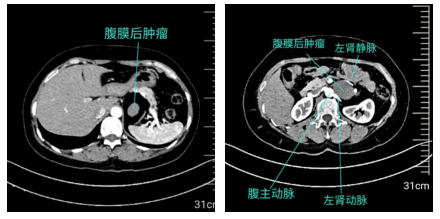

入院后,李广恩教授团队立即为王女士完善了腹主动脉CT造影(CTA)和上腹部增强CT检查,检查结果显示:腹膜后肿瘤与左肾血管分界不清,且紧邻胰腺、脾脏、腹主动脉等重要结构;更棘手的是,肠系膜上动脉存在“夹层”——血管内膜撕裂形成的假腔,如同在“生命管道”上凿出了一道裂痕,一旦术中操作不慎,可能引发大出血或肠缺血坏死。

李广恩教授介绍道:患者的肿瘤位于左肾动静脉之间,这些组织像“胶水”一样粘在本就菲薄的左肾静脉上,稍有不慎就会造成难以控制的汹涌出血,既要保证肿瘤“整块切除”,又要保留左肾静脉及肠系膜上动脉的完整性,避免夹层破裂以及切除左肾,只能一点点轻柔分离。